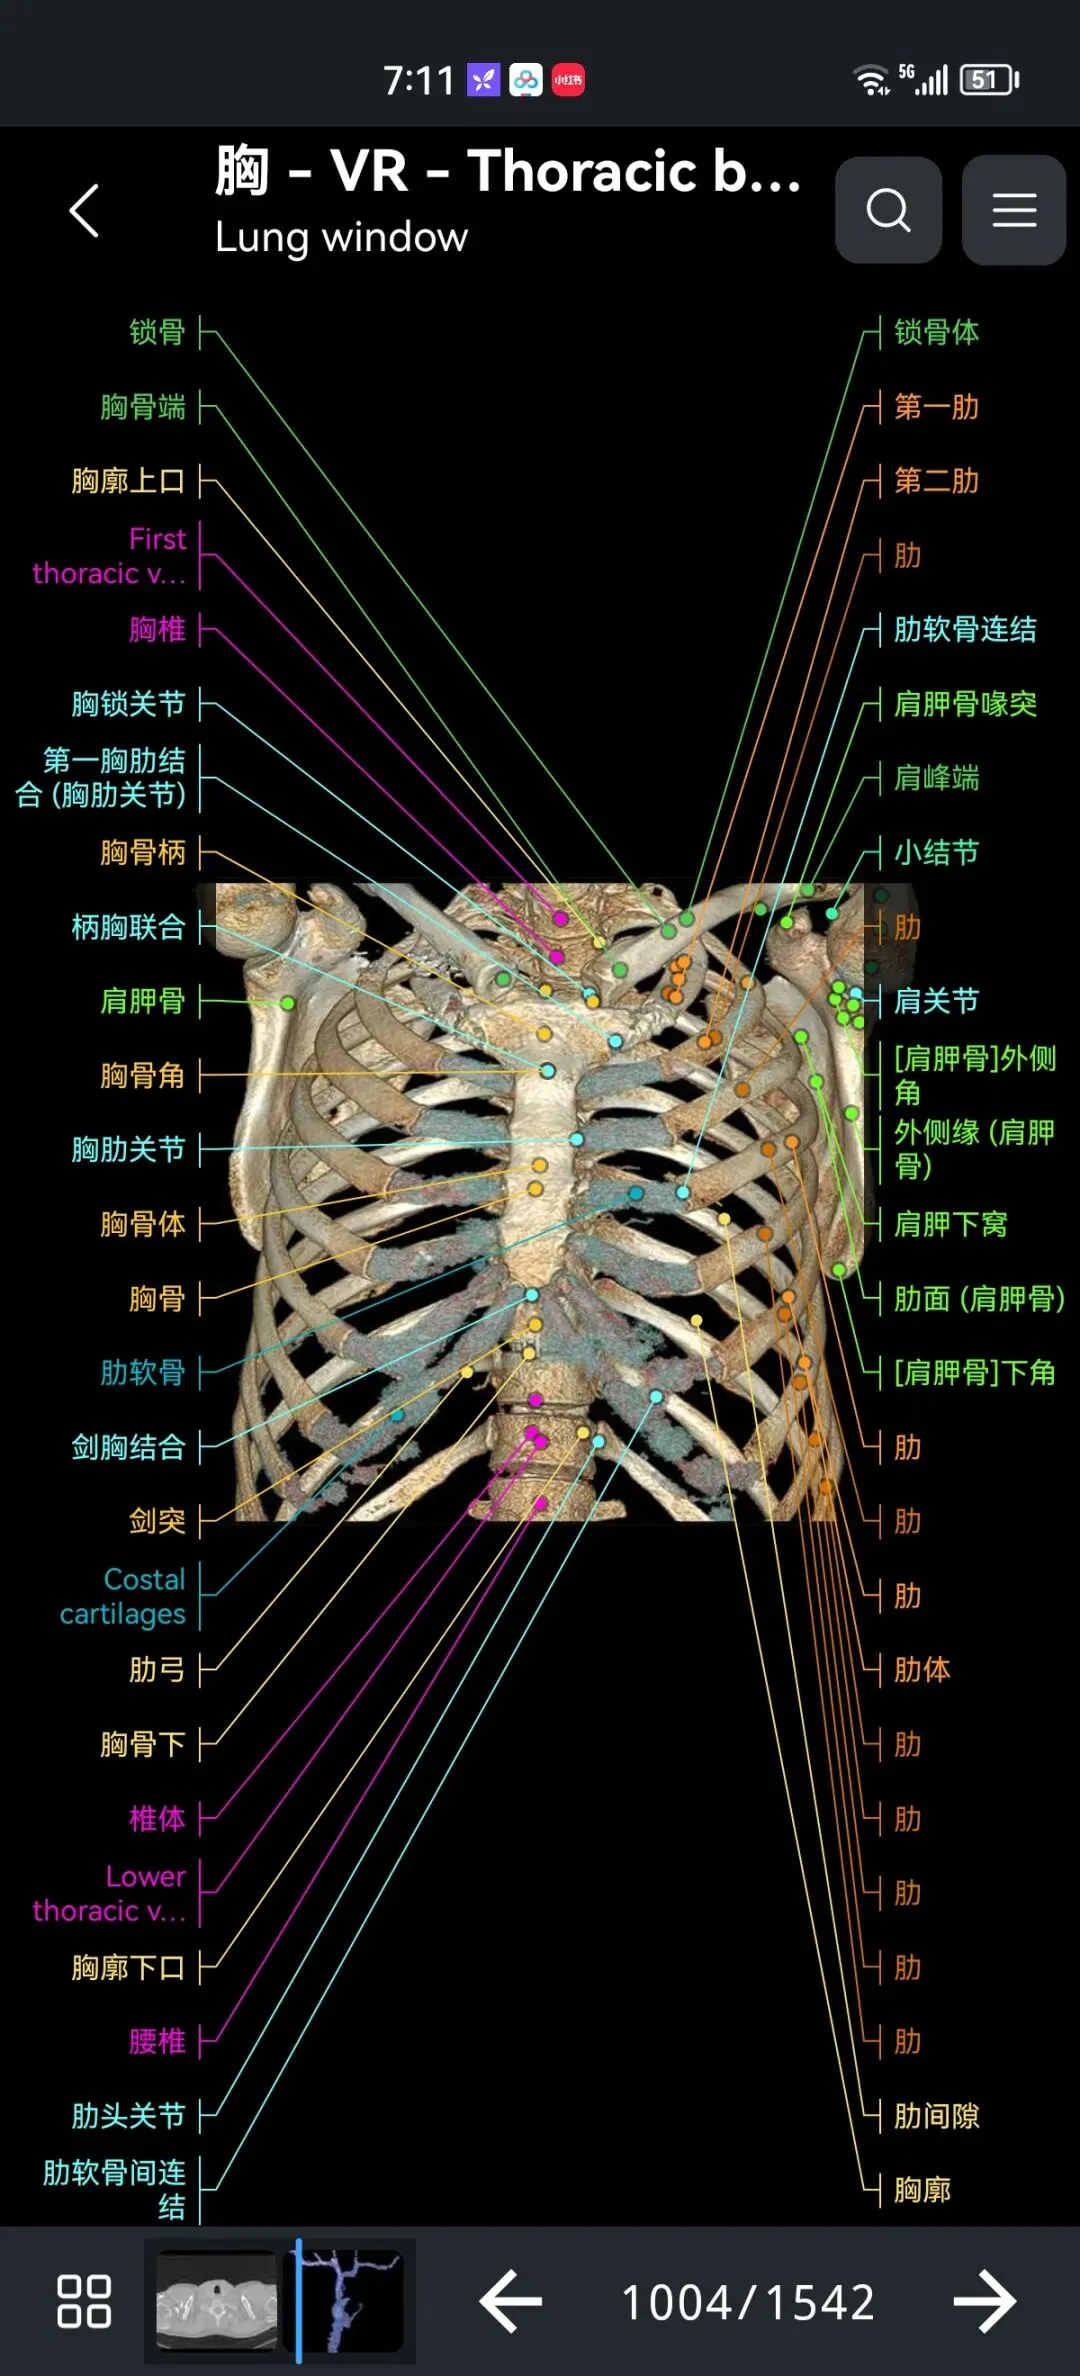

覆盖了X光、CT、MRI、断层大体解剖、核医学、介入造影、医学插图等多个模块,覆盖全身各个系统的影像解剖(正常解剖结构,无病例),其中的解剖结构高达87万个,结构标注超精细,超高清图像,历时两年研发设计完成✅。